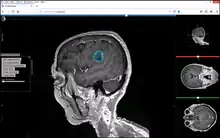

Studierfenster or StudierFenster (SF)[1][2][3] is a free, non-commercial open science client/server-based medical imaging processing online framework. It offers capabilities, like viewing medical data (computed tomography (CT), magnetic resonance imaging (MRI), etc.) in two- and three-dimensional space directly in the standard web browsers, like Google Chrome, Mozilla Firefox, Safari, and Microsoft Edge. Other functionalities are the calculation of medical metrics (dice score[4] and Hausdorff distance[5]), manual slice-by-slice outlining of structures in medical images (segmentation[6][7]), manual placing of (anatomical) landmarks in medical image data, viewing medical data in virtual reality, a facial reconstruction and registration of medical data for augmented reality,[8] one click showcases for COVID-19 and veterinary scans, and a Radiomics module.

Other features of Studierfenster are the automatic cranial implant design with a neural network,[9][10] the inpainting of aortic dissections[11] with a generative adversarial network,[12][13] an automatic aortic landmark detection with deep learning[14] in computed tomography angiography scans, and a GrowCut algorithm implementation for image segmentation.

The Metrics Module has been used to compare manual anatomical segmentations of brain tumors[30]